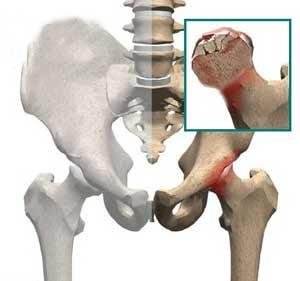

儿童股骨头坏死,又称股骨头骨骺软骨炎、股骨头无菌性坏死或扁平髋。是儿童常见的原因不明的软骨病,多发于2~12岁儿童,以退行性变或坏死开始,继后出现再生或重新钙化,最终出现股骨头的坏死。一开始表现为膝关节-髋关节痛,步行不便或跛行,患髋不能屈伸、内收。因为有的很隐匿,孩子只是有点疼,跛行两天,有像是没事了,只有磁共振才能发现股骨头的缺血水肿,本病早期诊断早期治疗十分重要,但又有几个家长愿意让孩子因为髋关节有点疼痛就去做磁共振呢?

1,对于儿童期出现的股骨头坏死主要与发育有关,特别是有髋关节半脱位或者是先天性的髋关节脱位,会导致股骨头部位出现异常的摩擦挤压,从而破坏股骨头的软骨面和周围的血液,就会导致股骨头坏死。

2,还有就是见于外伤,特别是*力暴**导致了股骨头股骨颈部位的骨折,髋关节脱位复位后,如果说治疗不当,也有说法是因为关节囊内出血,压力增大引起,后期也容易引起股骨头部位的血液破坏,从而引起了股骨头坏死的情况。